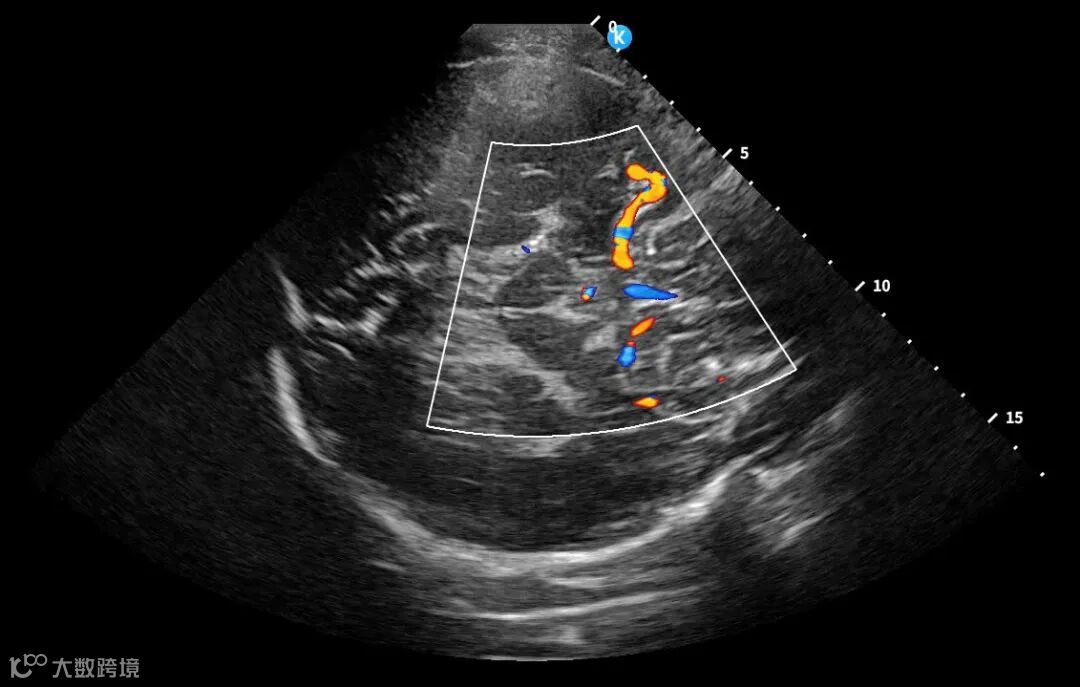

深圳鲲为科技有限公司是以突破性原创技术引领,并致力于下一代超分辨超声开发的专业影像设备公司。